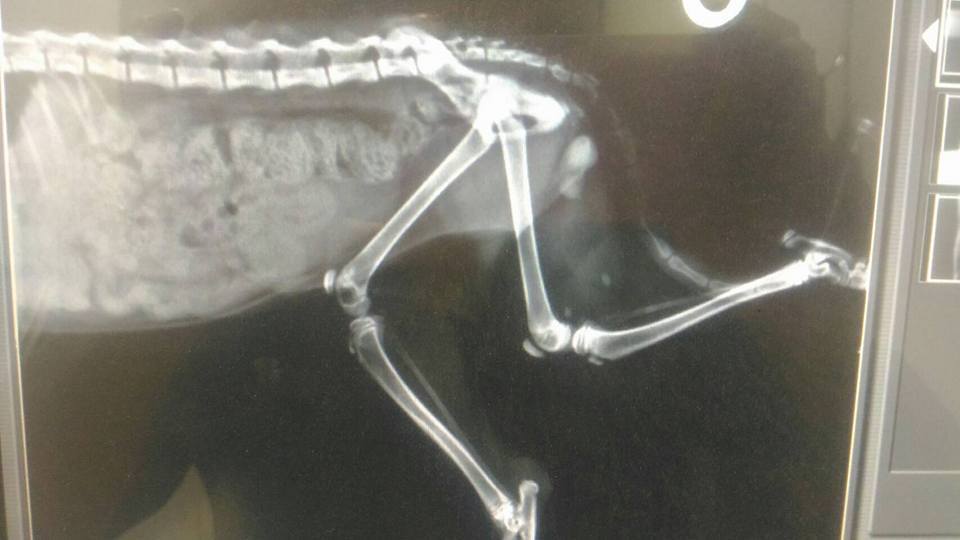

主題: 失明幼貓大腿被咬傷 流血見骨 指甲不見 申請者姓名: 李佳蔚 花色: 申請日期: 2017-11-15 18:02:09 申請者部落格: 申請者臉書網址: 所在縣市/合作醫院: 高雄市/銀星動物醫院 治療費用: 16000元 需求人數: 35人 已結案 (2024-06-01 13:21:04) 報名人員: 家有三色喵(已付款)、Rita Tsai x2(已付款)、beforn x2(已付款)、Leanne x2(已付款)、S(已付款)、Alice Chen(已付款)、Luc、Luc Chang(已付款)、胖胖米(已付款)、fnnny x20(已付款)、仔仔的媽(已付款)、薇薇安(已付款)、Ciara Ting(已付款)、Candyfloss Hi(已付款)、 候補人員: 動物病情說明: 拜託大家幫幫忙...

在9月30日的時候就發現小幼貓的後腿流血見骨。

貓咪捕獲後發現有:左眼弱視、右眼萎縮失明、後腿受傷見骨、前爪兩根指甲前端遭斷指剩下骨頭。

貓咪後大腿被咬傷流血見骨